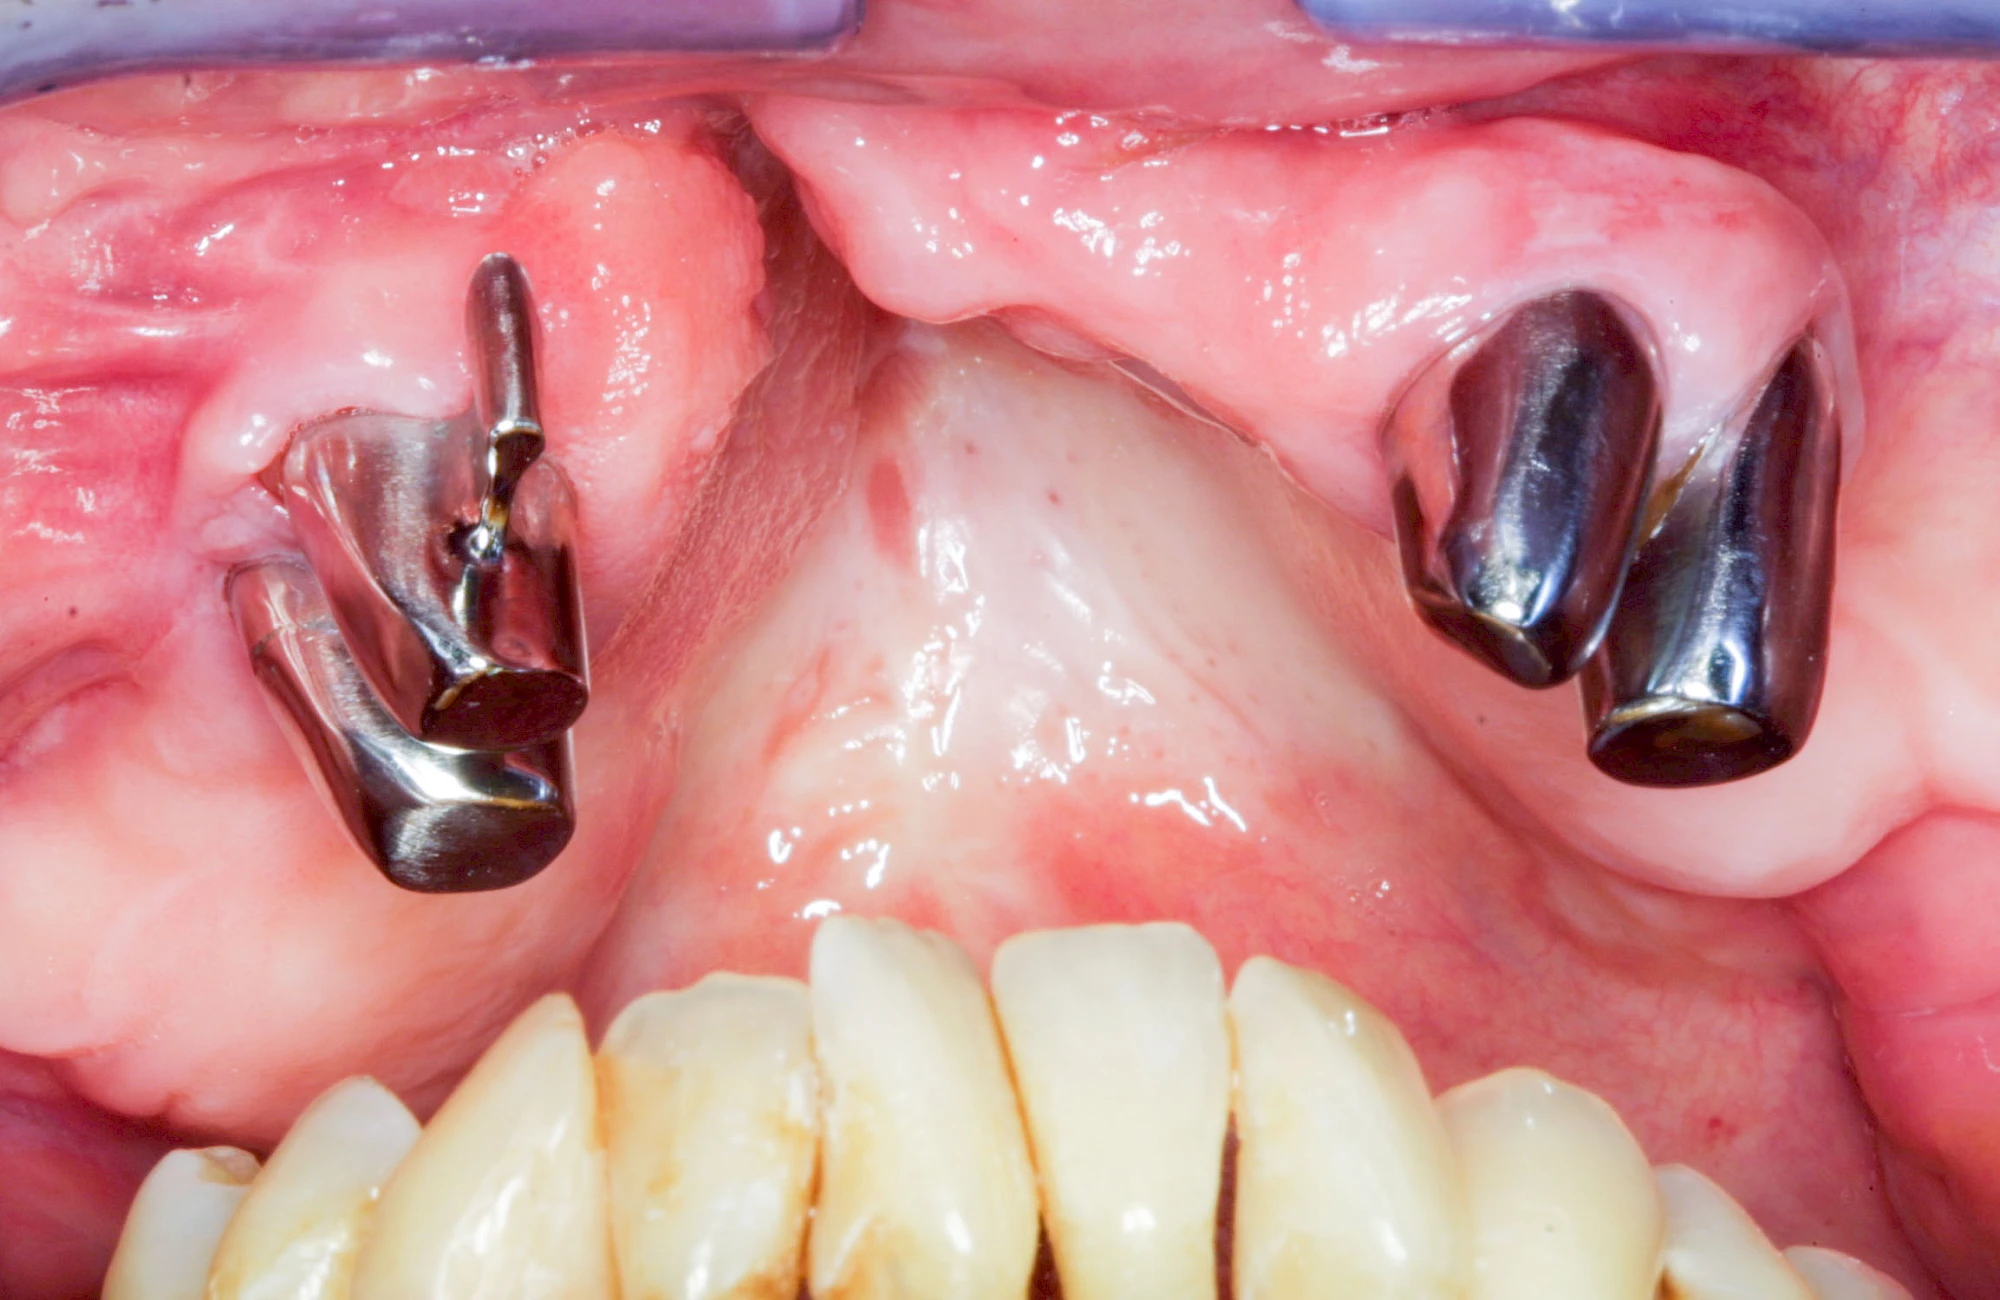

In seltenen Fällen schwindet nur der Knochen, aber nicht die bedeckenden Schleimhäute. In diesen Fällen spricht man von einem sogenannten "Schlotterkamm".